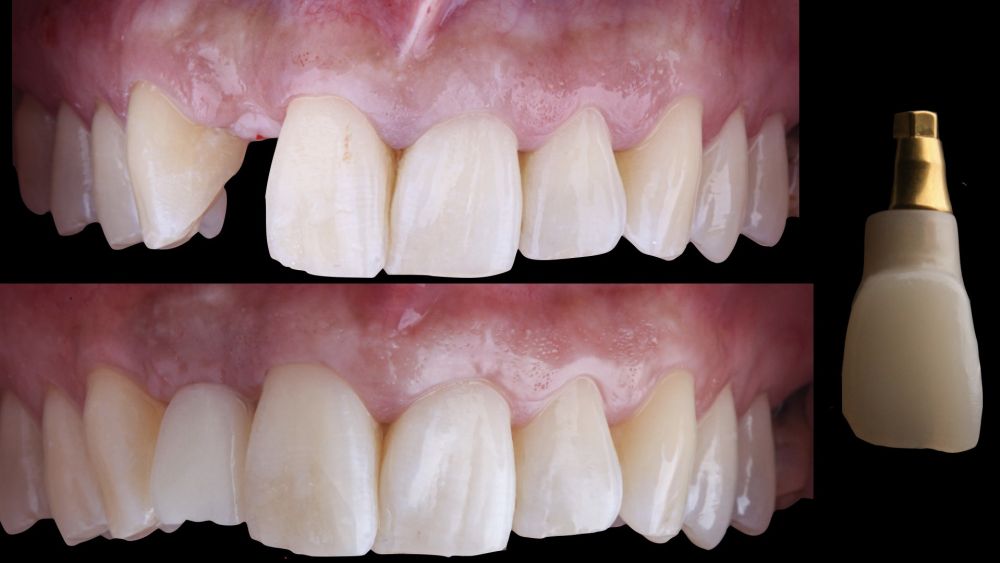

-Fase III: tres meses tras la colocación del implante, la situación del tejido blando era favorable (Figuras 5 y 6). Se tomó una impresión digital mediante escáner intraoral para la realización de un provisional atornillado de polimetilmetacrilato (PMMA). Respecto a la corona implantaria definitiva se realizó una restauración cemento-atornillada con una interfase de titanio nitrurado adaptando el diseño al perfil de emergencia ya consolidado con la prótesis provisional. La corona se realizó por CAD-CAM en zirconio con reducción completa y estratificación de cerámica feldespática de recubrimiento para zirconio (Figura 7).

El resultado clínico final fue satisfactorio cumpliendo las demandas estéticas del paciente. Los tejidos blandos estaban morfológicamente y dimensionalmente estables sin ningún signo de inflamación. Sin embargo, los cambios del tejido blando periimplantario (espesor volumétrico vestibular) fueron demostrados de manera cualitativa y cuantitativa (Figuras 8 y 9). En el postoperatorio inmediato (T1), la ganancia media obtenida al comparar T0 frente a T1 fue de 0,88 ± 0,15 mm con un incremento máximo de 1,1 mm. Al comparar T0–T2, se observó una ganancia media de 0,73 ± 0,23 mm. Es decir, se ha producido una contracción de volumen de 0,16 mm desde la colocación del injerto (T1) hasta pasado un mes y medio (T2).